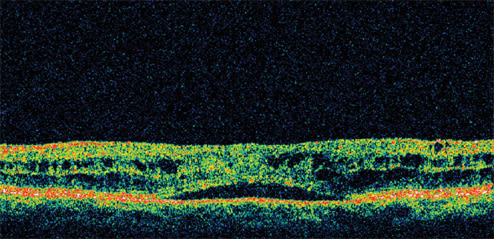

Figure 2. One month after starting treatment with nepafenac 0.1% (Nevanac, Alcon) qid, the patient's vision improved to 20/25 with significant reduction in her retinal thickness.

Presenting visual acuity was 20/40. Her IOP was 23 mm Hg and retinal thickness was 478 μm on OCT (Figure 1). She was treated with nepafenac qid for 6 weeks and tapered over the ensuing 6 weeks. Her vision improved to 20/25 by 1 month with significant reduction in her retinal thickness (Figure 2). By 12 weeks, her visual acuity had improved to 20/20 with a retinal thickness of 216 μm and a normal foveal contour. This represents a reduction in retinal thickness of 262 μm from her pretreatment status (Figure 3). However, she continued to report a mild reduction in contrast sensitivity.